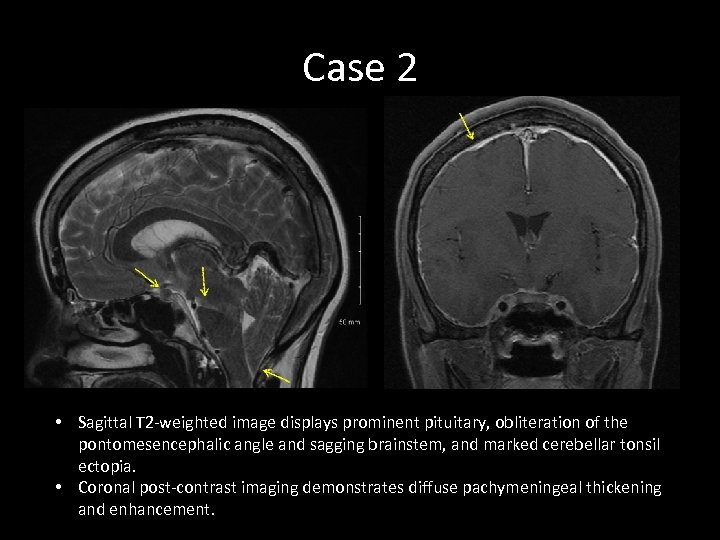

Case 2 • Sagittal T 2 -weighted image displays prominent pituitary, obliteration of the pontomesencephalic angle and sagging brainstem, and marked cerebellar tonsil ectopia. • Coronal post-contrast imaging demonstrates diffuse pachymeningeal thickening and enhancement.

Case 2 • Sagittal T 2 -weighted image displays prominent pituitary, obliteration of the pontomesencephalic angle and sagging brainstem, and marked cerebellar tonsil ectopia. • Coronal post-contrast imaging demonstrates diffuse pachymeningeal thickening and enhancement.